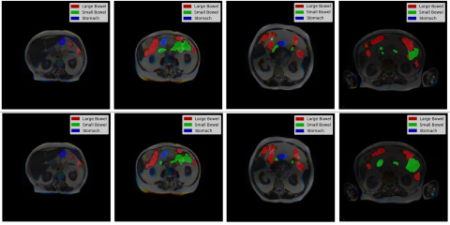

מחקרי מתמקד ברשתות עצביות עמוקות (DNN) לניתוח תמונות רפואיות, עם דגש על זיהוי אוטומטי, סגמנטציה ומיון במצבי הדמיה כגון MRI ו-CT. המחקר חוקר ומטמיע אדריכטורות שונות, כולל U-Nets ומודלים מבוססי טרנספורמרים, במטרה לשפר את הדיוק, היכולת להכליל ולספק אמינות קלינית.